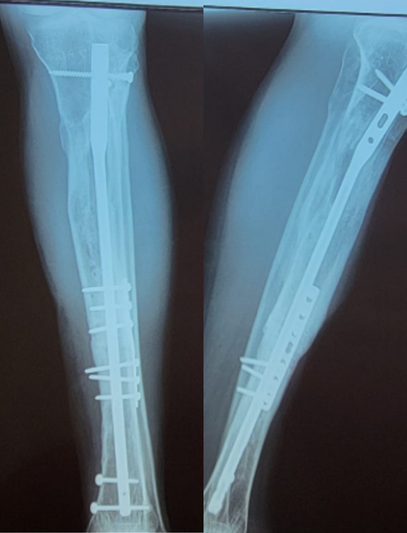

Tras un accidente de tránsito, Yessenia presentó una fractura expuesta con un defecto óseo de 10 cm en su pierna. Había recibido tratamientos previos sin éxito y su movilidad estaba en riesgo.

Con la técnica de osteogénesis por distracción y el uso de un tutor circular Ilizarov, se inició un proceso de regeneración ósea progresiva, acompañado de un seguimiento cercano.

Hoy Yessenia evoluciona favorablemente, conserva movilidad en su rodilla y tobillo, y está recuperando la independencia que pensaba perdida.